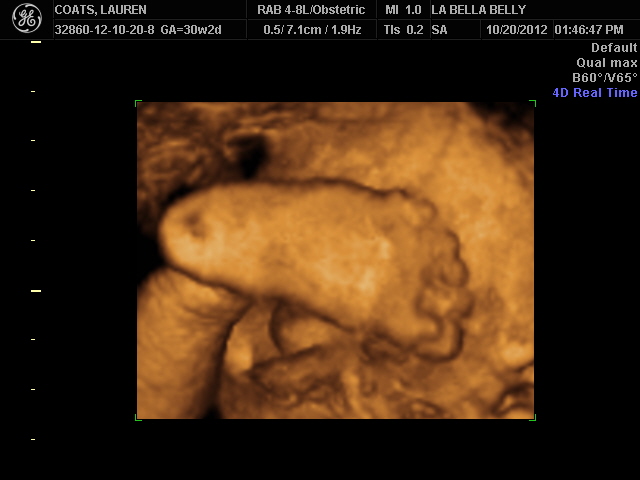

We got a fun 3D/4D sonogram today of baby Dayton! He had his feet covering his face most of the time, but he finally moved them for a second so that we could see his cute little lips & nose :)

We can't wait to meet you Dayton!! :)